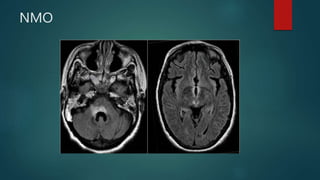

NMO